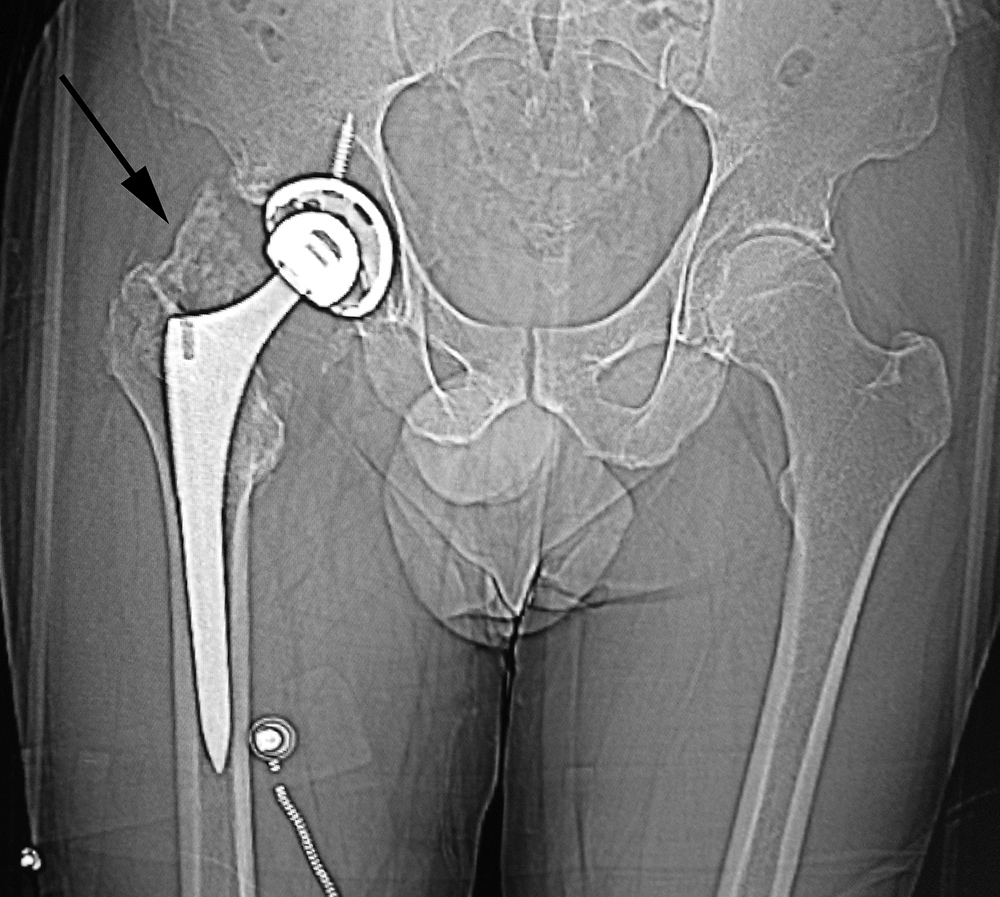

When local particulate matter becomes prominent and threatens or causes prosthesis failure, it is called particle disease or metallosis (figure: particle disease in right hip implant; figure: particle disease left hip CT; figure: left hip polyethylene liner wear; figure: metal-on-metal prosthesis with metallosis). See the discussion of adverse reaction to metal debris in Orthopedic medical devices and cross-sectional imaging: protocols and artifacts - MRI.

68 year-old man with particle disease from a worn out left hip prosthesis. Bony destruction (arrows) is in the left supra-acetabular region and in the left greater trochanter with a pathologic fracture. |

68 year-old woman with left hip metal-on-metal prosthesis. Bony erosions (arrows) are evident on the greater and lesser trochanters from probable metallosis with pseudotumor formation. |